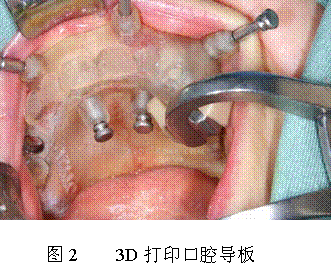

再如種植牙齒,目前種植一顆牙需要一兩(liang) 萬(wan) 塊,種植體(ti) 本身就像一個(ge) 螺絲(si) 一樣,怎麽(me) 樣才能把假牙精確地種植在牙床上,在沒有用導板之前就完全要靠醫生的經驗,所以有的醫生高明收費也相對要高,這就是為(wei) 什麽(me) 種植一顆小小的牙需要花費那麽(me) 高的原因,一顆假牙的重量就二三十克,價(jia) 錢比黃金還要貴,實際上它的材料就是原始的不鏽鋼、鈷鉻合金或鈦合金等。但如果有了導板的話(如圖2所示),種植牙的難度就會(hui) 大大降低了,普通的醫生也能做到,這樣就能降低假牙種植的花費。